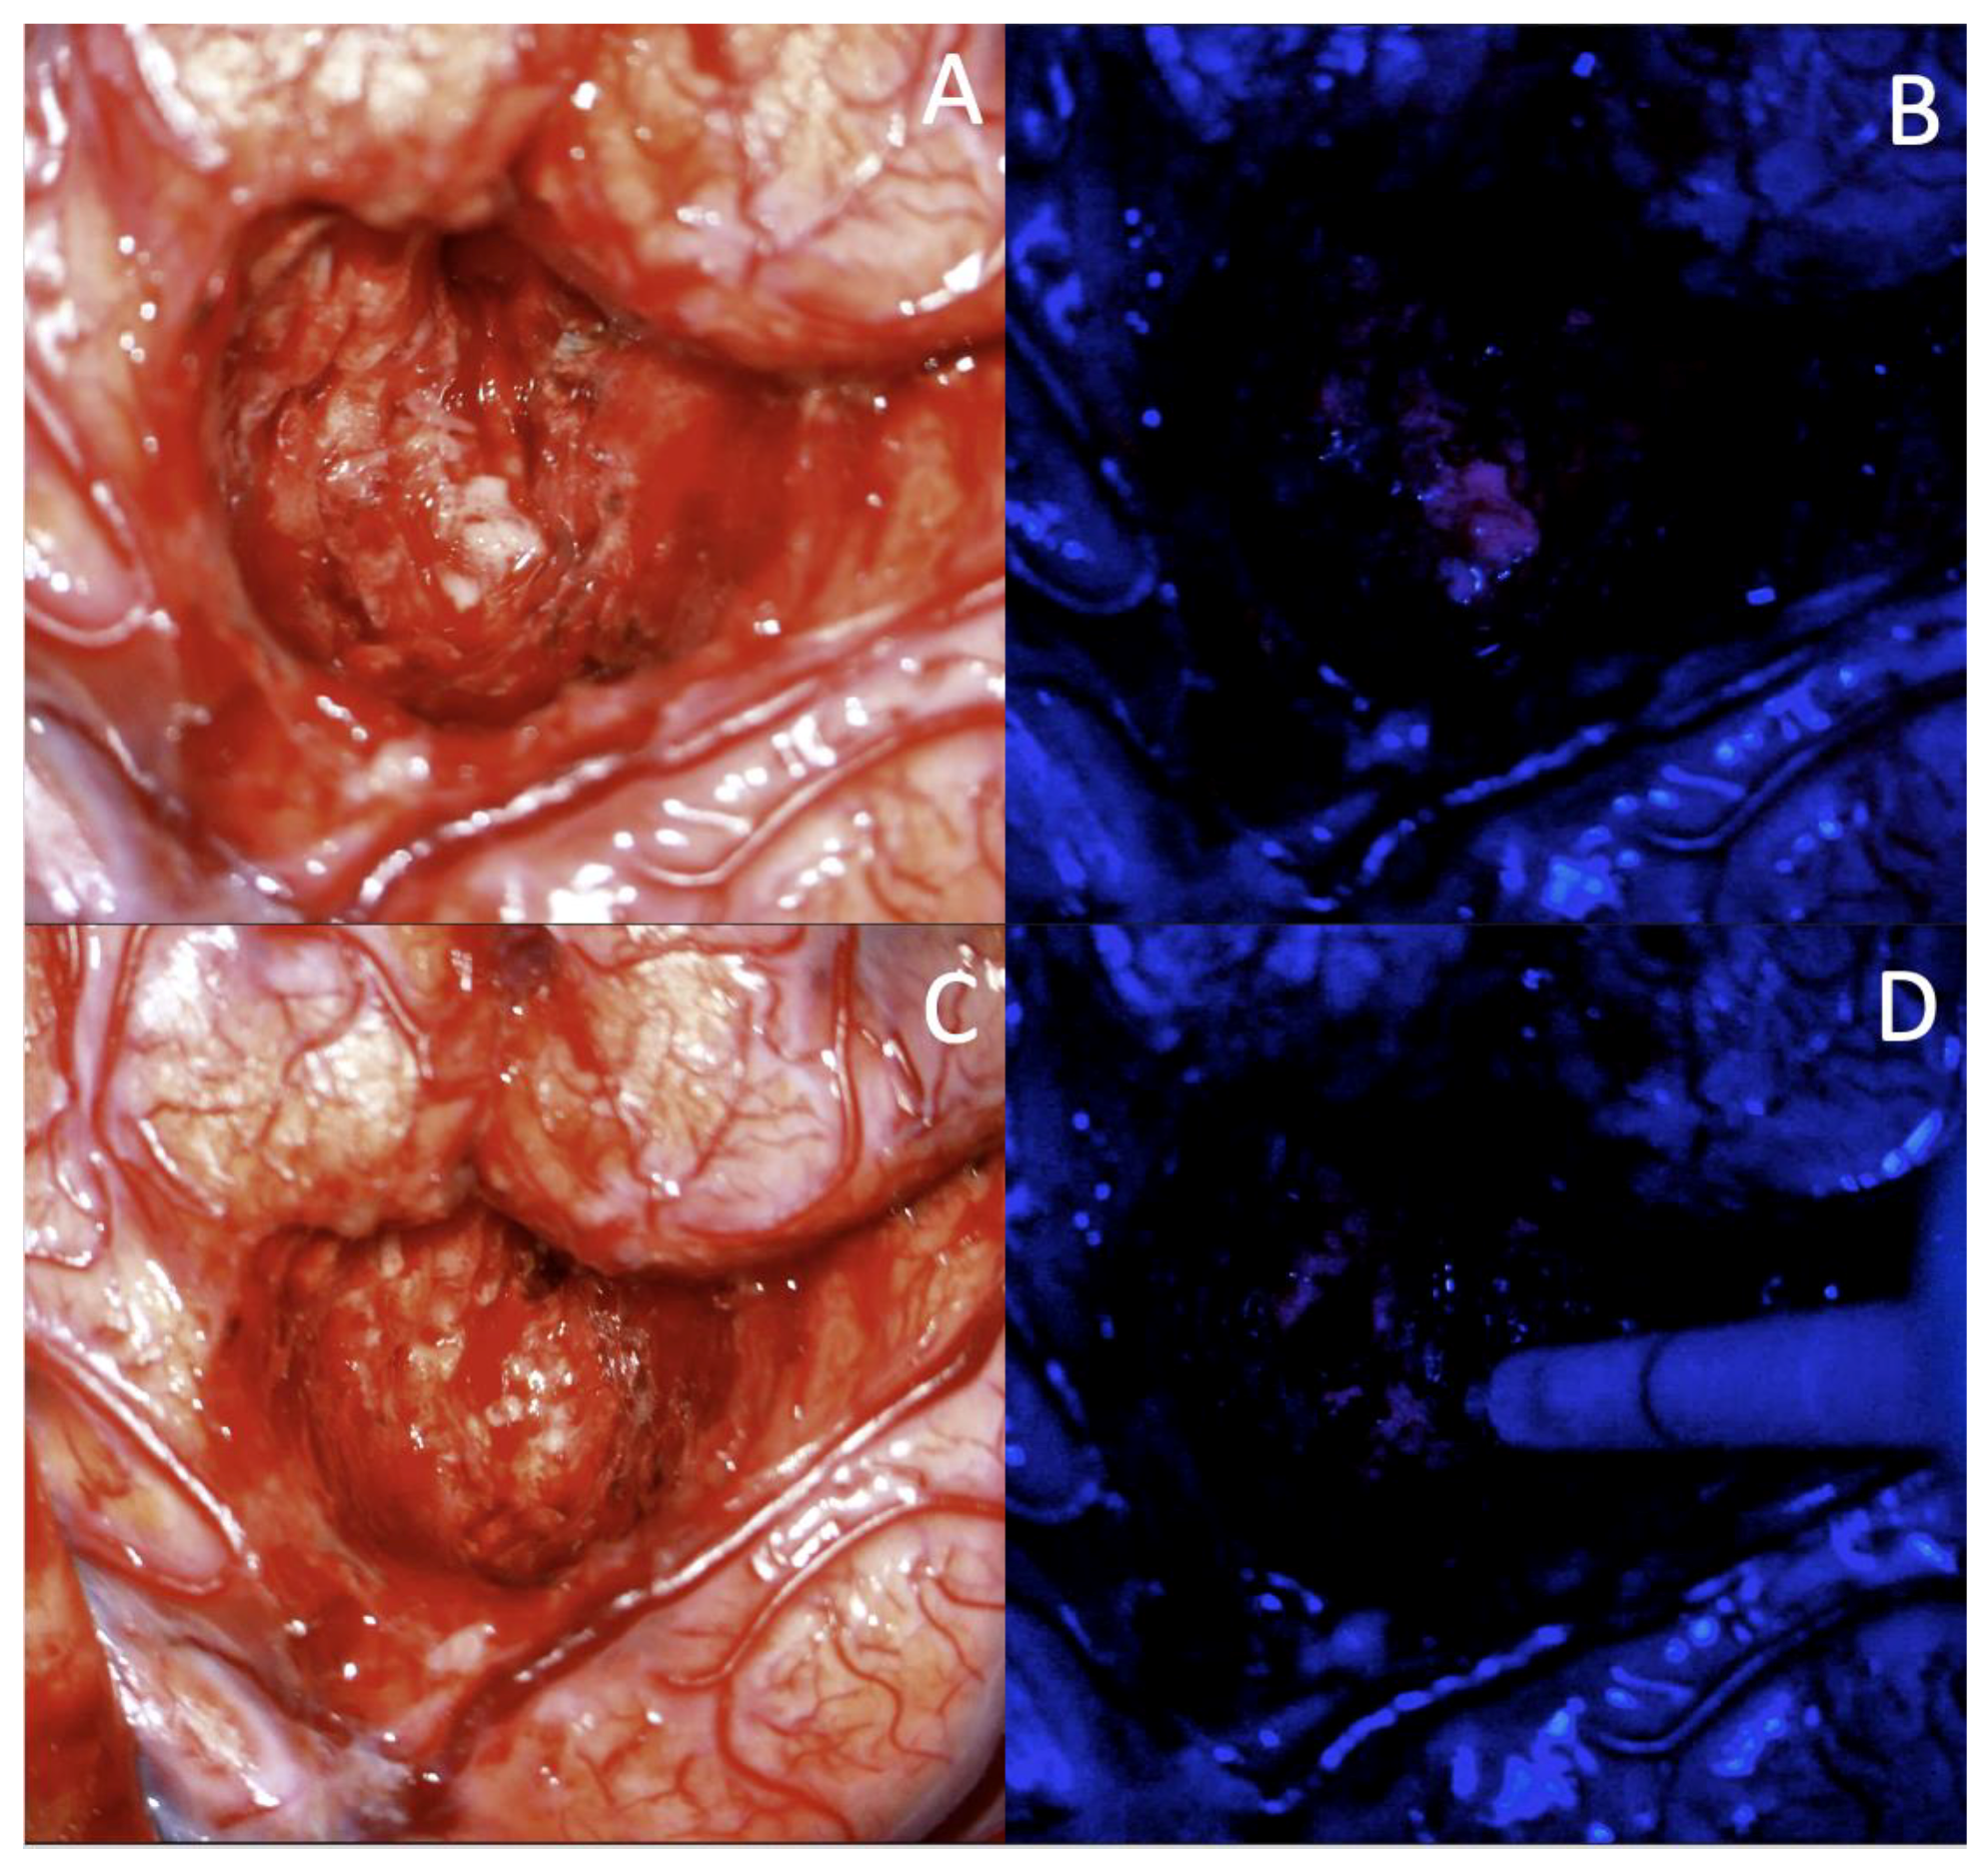

- Stummer, W.; Pichlmeier, U.; Meinel, T.; Wiestler, O.D.; Zanella, F.; Reulen, H.J. Fluorescence-guided surgery with 5-aminolevulinic acid for resection of malignant glioma: A randomised controlled multicentre phase III trial. Lancet Oncol. 2006, 7, 392–401. [Google Scholar] [CrossRef]

- Zhao, S.; Wu, J.; Wang, C.; Liu, H.; Dong, X.; Shi, C.; Shi, C.; Liu, Y.; Teng, L.; Han, D.; et al. Intraoperative fluorescence-guided resection of high-grade malignant gliomas using 5-aminolevulinic acid-induced porphyrins: A systematic review and meta-analysis of prospective studies. PLoS ONE 2013, 8, e63682. [Google Scholar] [CrossRef]

- Della Puppa, A.; De Pellegrin, S.; d’Avella, E.; Gioffrè, G.; Rossetto, M.; Gerardi, A.; Lombardi, G.; Manara, R.; Munari, M.; Saladini, M.; et al. 5-aminolevulinic acid (5-ALA) fluorescence guided surgery of high-grade gliomas in eloquent areas assisted by functional mapping. Our experience and review of the literature. Acta Neurochir. (Wien) 2013, 155, 965–972, discussion 972. [Google Scholar] [CrossRef]